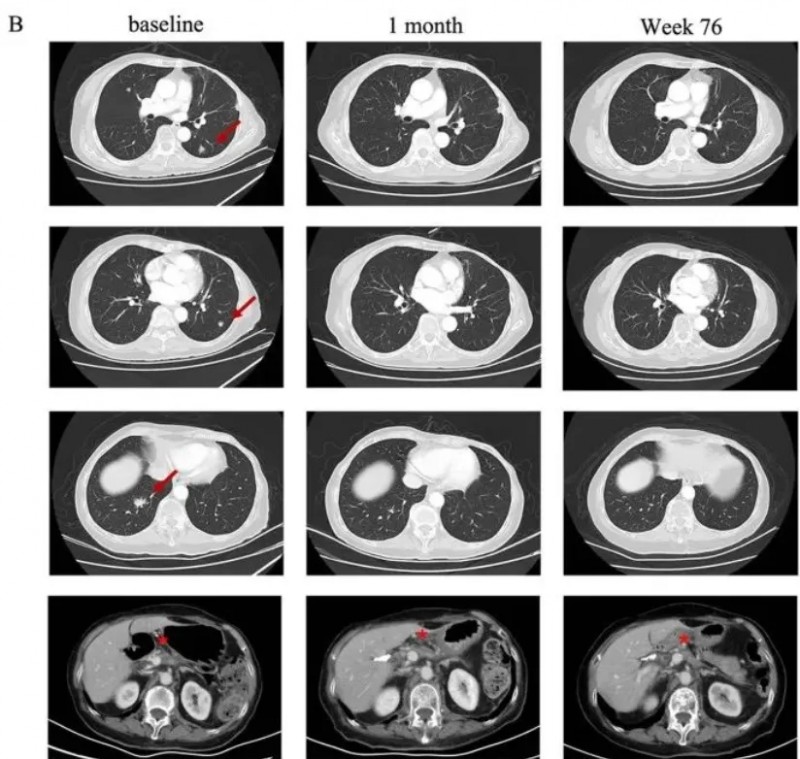

结果令人振奋:依据RECISTv1.1标准,患者在CT041输注后第4周即达部分缓解(PR),后续肺部转移病灶完全消失,实现完全缓解(CR)。截至2023年7月末次随访时,患者仍持续维持缓解状态,凸显satri-cel在胰腺癌治疗中显著的抗肿瘤活性与持久疗效。

▼该患者CT041治疗前后肺部病变的放射学评估

▲图源“J Hematol Oncol”,版权归原作者所有,如无意中侵犯了知识产权,请联系我们删除